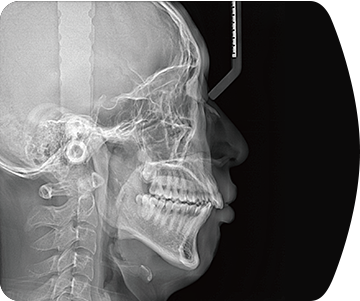

采用高性能CMOS探测器,最大FOV可达16x9cm星垂视野并支持无极可调,最小体素0.05mm。头颅采集模式,支持3s超快速扫描,最小像素99um,保证优质影像快速采集。

临床样片